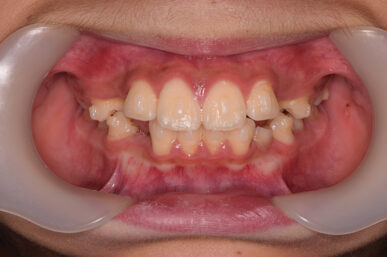

• Before

治療開始が遅くてこのままでは犬歯の生えるスペースが不足していて八重歯になるところでしたが、アライナー矯正で素早く歯を動かして犬歯が生えてくるスペースを作ることで八重歯にならずに済みました。

八重歯のケースは永久歯の抜歯が必要になることもありますが、避けることができました。